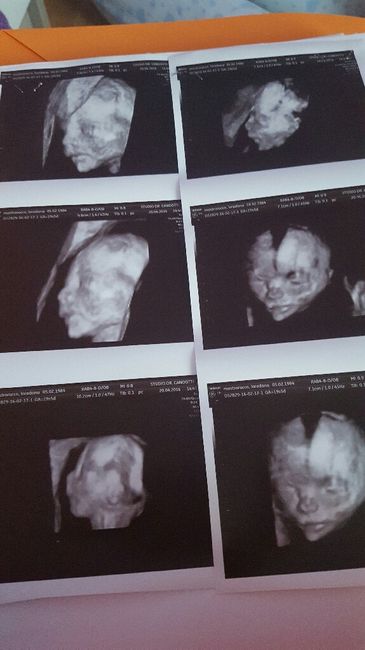

Ragazze ieri ho fatto l eco!! Credevo di essere a 9+6 mentre invece la dottoressa mi ha datato 10+2 ho visto il mio piccolo fagiolino ormai già troppo cresciuto per...